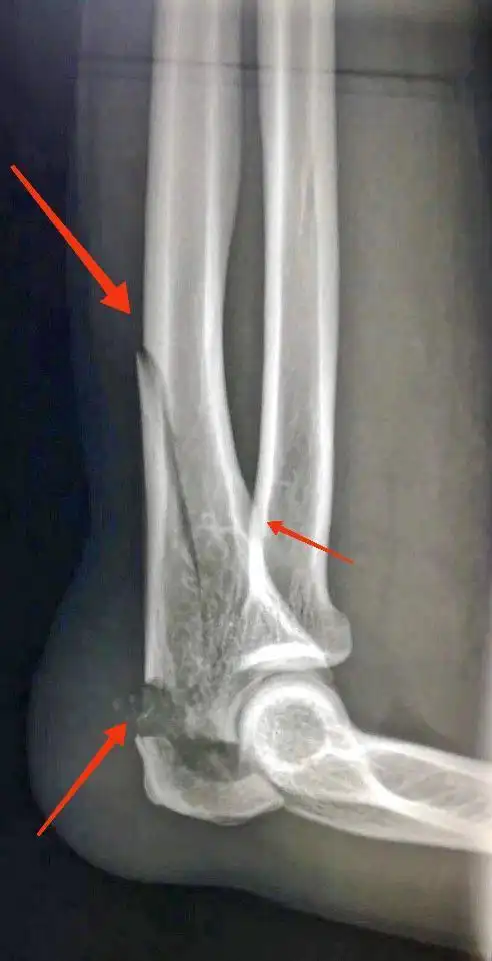

小腿骨小腿骨折的采集图像及钢板内固定手术治疗. 折断胫骨和腓骨照片

创伤左肘关节脱位伴尺骨冠状突骨折